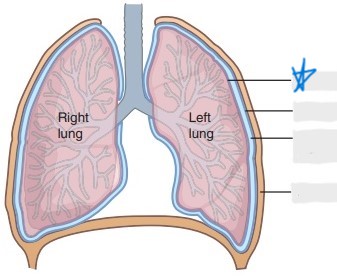

visceral pleura

parietal pleura

pleural cavity